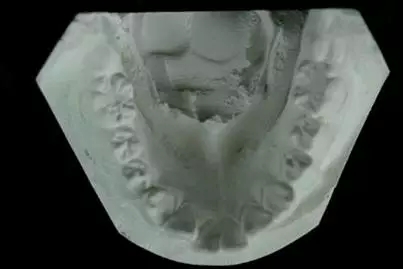

【口腔正畸】制作記存模型

記存模型的用途:

(1) 間隙總量分析的計算

(2) 評估和記錄牙體解剖形態(tài)

(3) 評估和記錄牙弓形態(tài)

(4) 記錄上,下頜牙齒的尖窩關系

(5) 評估和記錄<牙合>曲線

(6) 在<牙合>架的情況下評估咬<牙合>

(7) 計測評價治療中的進展情況

(8) 檢查牙<牙合>異常情況

(9) 為治療前,治療完成和完成后數(shù)年提供記錄,以研究治療過程.